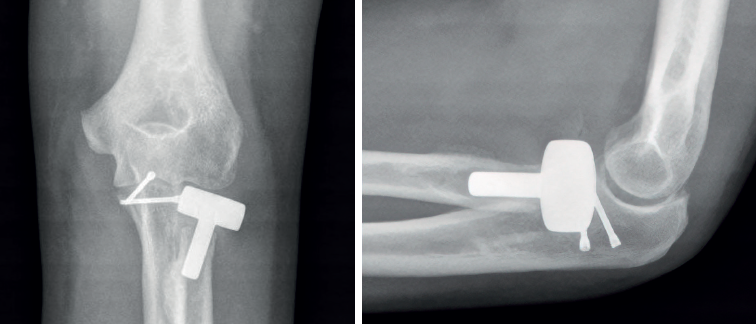

- Mason III: fracturas conminutas, desplazadas, con bloqueo mecánico a la rotación y potencialmente irreparables. La fijación de aquellas fracturas de la cabeza del radio en 3 partes (diáfisis y 2 fragmentos articulares) es propensa a un fracaso temprano de la fijación, a una falta de consolidación y a una rotación limitada del antebrazo(15). Es por ello por lo que, en estos casos, puede ser preferible la resección de la cabeza radial seguida de la colocación de una prótesis modular. Doornberg et al.(16) han sugerido que el borde lateral de la coronoides es un punto de referencia útil para dimensionar la cabeza del radio y, en general, la prótesis no debe quedar más de 1 mm proximal a este punto de referencia (Figura 5).